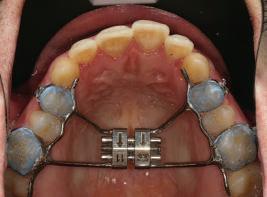

Пациентът постъпи в клиниката с молба за тотална рехабилитация на усмивката. Той не харесваше централ ните си резци, които според него бяха твърде къси и квадратни. Имаше раз стояние от медиално и дистално на латералните му резци. Друго сериоз но оплакване бе свързано с металоке рамичната корона на зъб 12, която бе жълтеникава и неестетична, като цяло не харесваше вида на венците си и както самият той се изразяваше, „вижда се прекалено много от венците при усмивка“.

След диагностиката бяха направени екстра- и интраорални снимки, както и рентгенографии; професионалното почистване бе от изключителна важ ност, бяха дадени и инструкции за лич на орална хигиена. Бе направено интра орално сканиране с Medit i500. Цялата тази информация бе използ вана в приложението Smilecloud за 2D биометричен дизайн. В приложението са налични естест вени форми на зъбите и щом бяха под брани зъби и бе направен дизайн

библиотеката на Exocad. Струва си да се отбележи, че 2D дизайнът от Smile Cloud бе спазен до последния детайл в Exocad smile creator с цел да се създаде 3D obj файл със зъбните форми. След като естетичният дизайн бе готов в model creator модула на Exocad, адитивен 3D мок-ъп модел бе експорти ран и принтиран от принтер Formlabs 3. Моделът бе използван за направата на силиконов водач, за да се изготви мо тивационен мок-ъп в устата на паци ента и да се оценят естетичните па раметри. След като пациентът одобри вида на усмивката си, мок-ъпът бе използван за финализиране дизайна на усмивка та. Мок-ъпът бе използван също така като водач по време на мекотъканна та хирургия, както и при препарация на зъбите.

Препарираните зъби бяха импорти рани в Exocad и насложени върху ес тествените форми от биометричния дизайн, като така стана ясно дали зъ бите са били препарирани коректно. По този начин зъболекарят и зъботехни кът работят в една и съща екосистема и резултатът е оптимален. С короната се справихме чрез диги тална редукция на циркония в Exocad, като по този начин на практика създа дохме циркониево кепе, след което про изведохме фасета от IPS Empress Cad Multi. Кепето от Katana Zirconia на зъб 12 с букално послойно нанесена керами ка бе фрезовано (послойното нанасяне бе направено, за да се подобри връзката и да се осигури адхезивно циментиране на фасетата към циркониевото кепе, както и за да се напасне цветът към този на съседните зъби). При първото сканиране регистрирах ме цялата горна зъбна дъга, така че, ко гато се наложи да сканираме повторно, бе изтрит и сканиран наново само зъб 12, тъй като венците не бяха отдръп нати при второто сканиране.

Една седмица след препарацията на зъбите и циментирането на цирко ниевото кепе бяха изработени 12 IPS Empress Cad Multi фасети. Макро- и микротекстурата на фасе тите бяха направени на ръка, след кое то бяха нанесени 3D характеризации с боички, а полирането отново бе напра вено ръчно, за да им се придаде естест вен и естетичен вид. Предизвикателството тук беше короната да има същите оптични характеристики като тези на остана лите зъби при естествена светлина, през поляризационен и флуоресцентен филтър. 3D принтерът бе Fromlabs, софтуерът за фрезоване – Mill Box, а фрез апаратът –imes icore CORiTEC 350i. В крайна сметка постигнахме ес тествен вид на усмивката с натурал на зъбна морфология при изцяло диги тален протокол, при който дизайнът бе направен първоначално и през всич ки етапи на лечението се придържахме към него до самия край Излишно е да отбелязваме, че всички сме удовлетворени от постигнатото! Преди След Победител в категория „Клиничен случай с изцяло дигитален протокол“ в конкурса „Усмивка на годината 2022“

11Dental Tribune Bulgarian Edition / октомври 2022 г. Преди лечението Фиг. 1 Фиг. 2 Фиг. 3 Фиг. 4 Фиг. 5 Фиг. 6 Фиг. 7 Фиг. 9 Фиг. 10 Фиг. 11 Фиг. 8 Фиг. 12 Фиг. 13